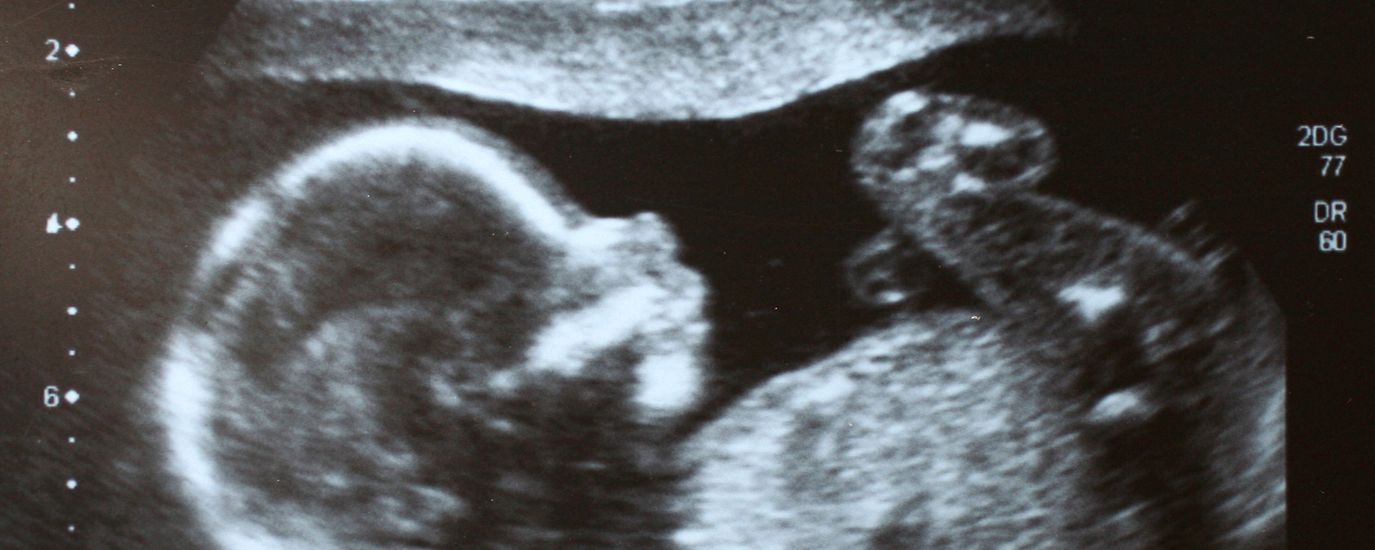

Sonografie und CTG

Bei einem normalen Schwangerschaftsverlauf sind 3 Ultraschall-Untersuchungen vorgesehen, jeweils 1 pro Schwangerschafts-Drittel. Dafür tragen wir die Kosten.